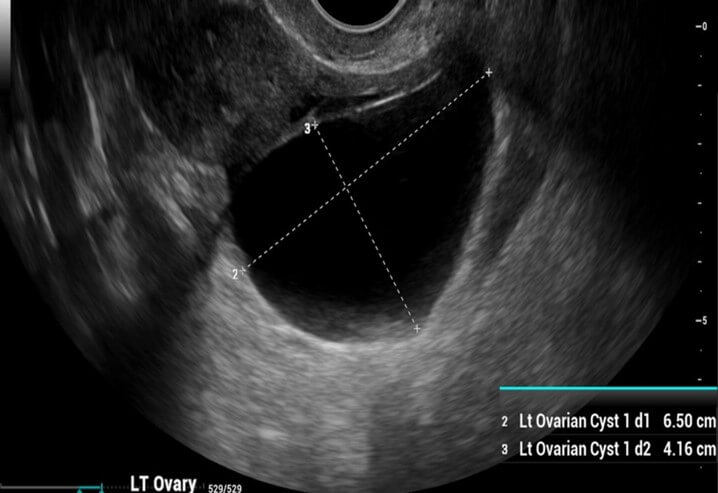

Transvaginal Ultrasound (TVUS)

Transvaginal ultrasound is the gold standard initial imaging modality for evaluating ovarian cystic masses.

Benign Ultrasound Features

• Unilocular cyst

• Thin, smooth walls

• Anechoic (clear fluid)

• No solid components

• No internal blood flow on Doppler

Common Ultrasound Patterns

• Hemorrhagic cyst: Reticular or lace-like internal echoes